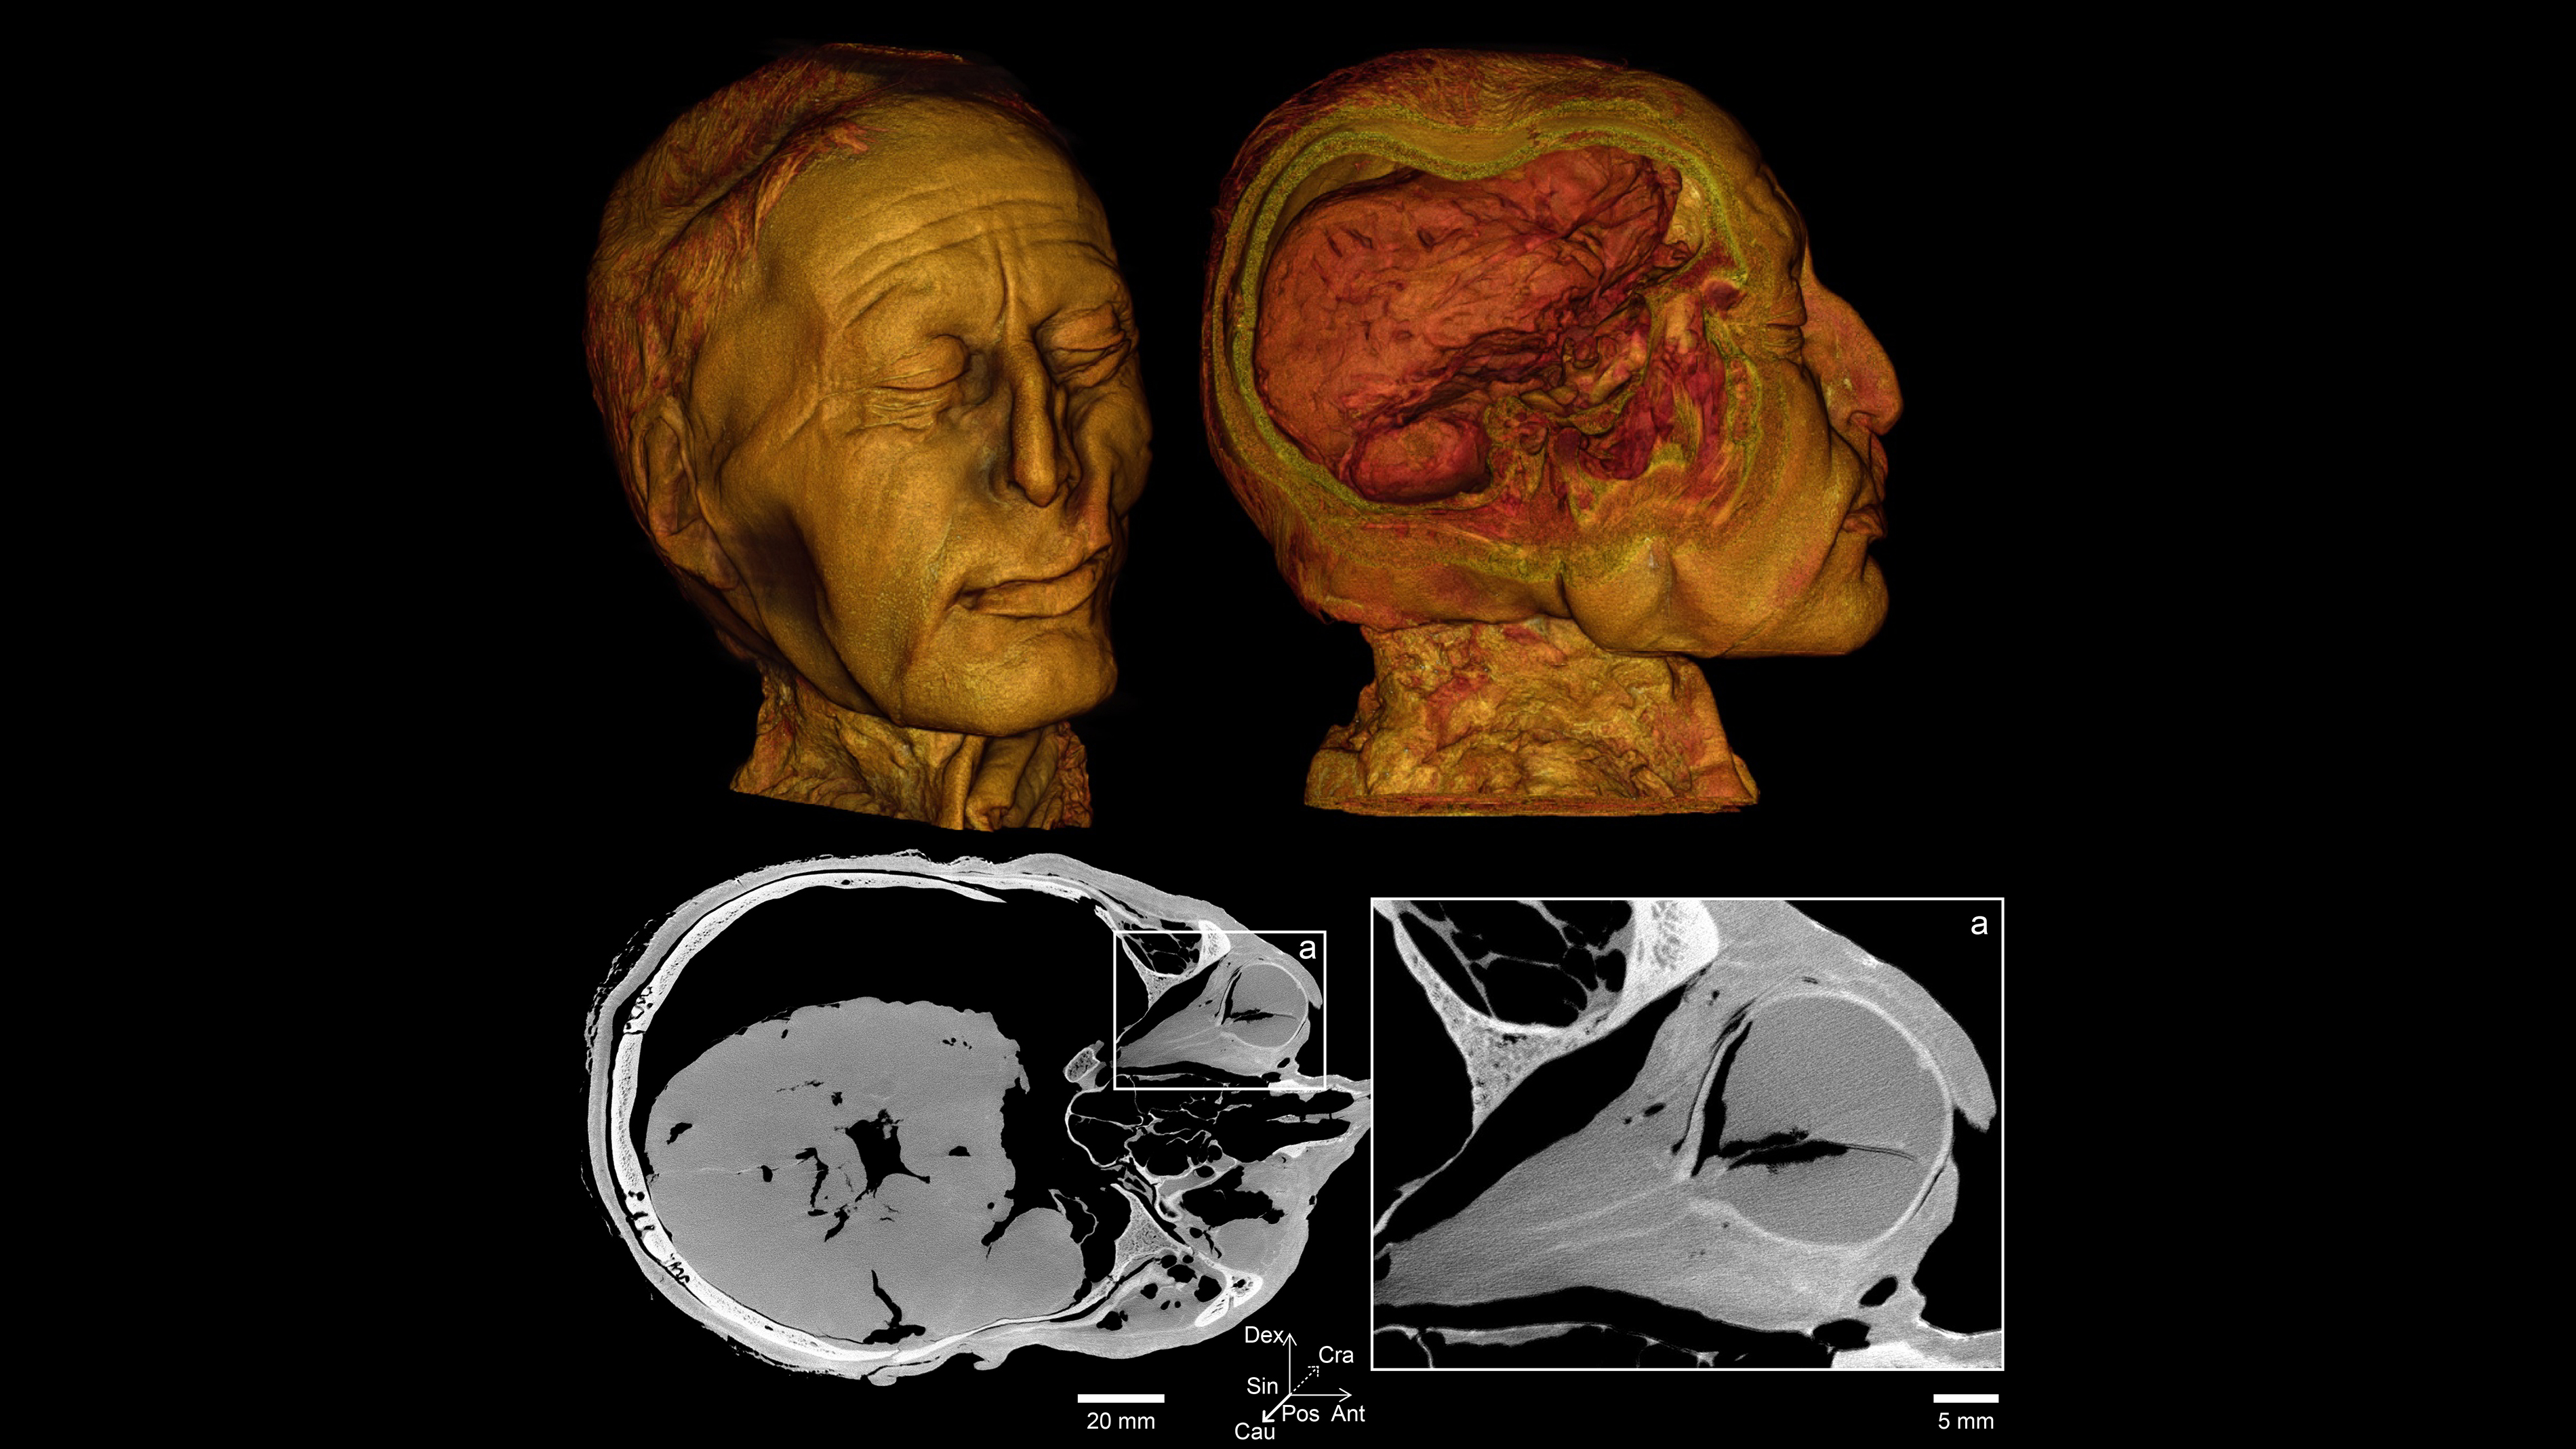

Men mandag den 22. april blev hovedet af det 2400 år gamle moselig Tollundmanden kørt fra Museum Silkeborg til Institut for Retsmedicin på Aarhus Universitet. Her gennemgik det berømte hoved grundige undersøgelser i både en klinisk CT-scanner og i universitetets nye mikro-CT-scanner, som kan tage billeder med meget stor detaljegrad.

Hovedet har været scannet én gang før – i 2002. På de gamle scanninger kunne man kun se tænderne som utydelige pløkker. Sammenligner man de nye scanninger med de gamle, er det fuldstændig som at have fået nye briller, siger Ole Nielsen. Opløsningen i de nye billeder er 422 gange bedre end i de gamle. Det gør en forskel.

”De nye scanningsbilleder er så flotte på grund af den gode kontrast, som gør det nemt at se forskel på forskelligt væv,” forklarer Kasper Hansen.

”Fordi Tollundmanden har ligget i en syrlig mose i over 2000 år, er meget af hans knoglemineral udvasket. Derfor er kontrasten mellem knogler og det bløde væv mindre end normalt. Men på en mikro-CT-scanner kan vi opnå bedre kontrast på de forskellige væv og se mange flere detaljer,” forklarer forskeren:

”Forskellen på en almindelig CT-scanner og en mikro-CT-scanner er som at gå fra et gammelt digitalkamera til et splinternyt.”

Den nye scanner adskiller sig fra universitets andre mikro-CT-systemer, fordi den både kan scanne små prøver ved ultrahøj opløsning og producere billeder af store genstande – som et helt hoved fra et oldtidsmenneske, påpeger lektor Henrik Lauridsen.

- Micro-CT er en 3D-billeddannelsesteknik, der bruger røntgenstråler til at se inde i et objekt, skive for skive. Det tager lang tid – til gengæld har billederne tårnhøj opløsning og stor detaljegrad.